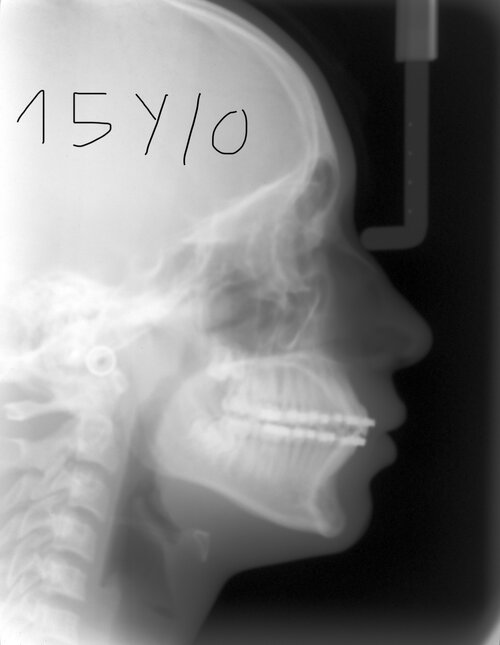

so i just remover my braces few months ago and to prevent the relapse, they put me a fixed retainer for the bottom teeth and a clear retainer for the top. I started my orthotropic treatment at 10 and i’m now 15. When i look my family members, they have a pretty good jaw area except me so i did some researches and i found that braces and retainers, do an hypomobility of the mandibule, so basically it reduces the probability of high development of the mandibule (forward growth) and my palatine expansion. I saw some ppl who wore braces too and still got a very good jaw area, like Ehren. So i just researched if Ehren did surgery, and its a pretty controversial question.

In my case, it feels like it’s over for me like i have a so bad jaw area, my salivary glands are so exposed, recessed chin, low hyoid, i stock a lot of fat in face even with around 16-17% body fat, i don’t consume a lot of sodium for water retention…

I asked ChatGPT btw about my radios and he told me that when i was 10 i got potential, but i got fucked by orthodontic treatment

So im asking you, how to promote a good growth of the mandible even if im nerfed asf (no surgery) ? and does it never begun for me?